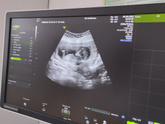

6 сентября 2022 08:50 Вот и узи прошла , первый скрининг все в норме . Я очень рада, ещё не известно кто лежит главное здоровый?

30 августа 2022 07:20 Всем привет! На следующей неделе у меня будет первый скрининг ! Интересно как там вырос ребенок ? не терпится увидеть .